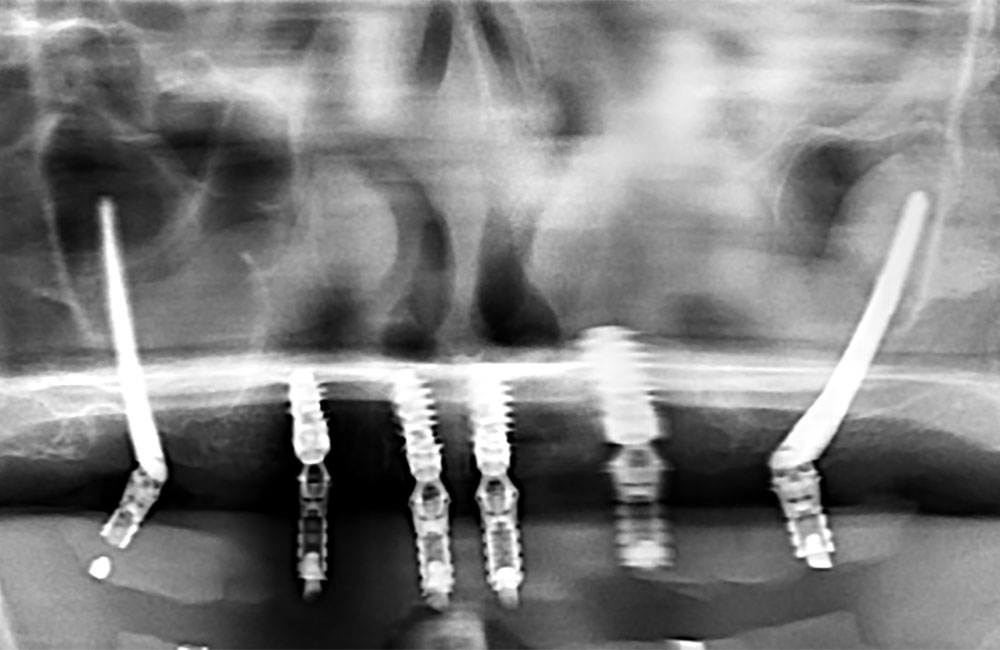

他院でザイゴマインプラント治療を受けた後、仮歯の噛み合わせが悪いため噛みづらく顔貌も変わってしまった。また頬に違和感を感じたため当院を受診。

術前のパノラマX線画像

左右のザイゴマインプラントが頬骨から大きく飛び出し頬を触ると違和感がある -

術後のパノラマX線画像

前方のインプラントは残し、他院埋入のザイゴマインプラントを除去し、同時に新しいザイゴマインプラントを適切な位置に再埋入を行っております。治療後数年経過しておりますが良好な状態を保っております。